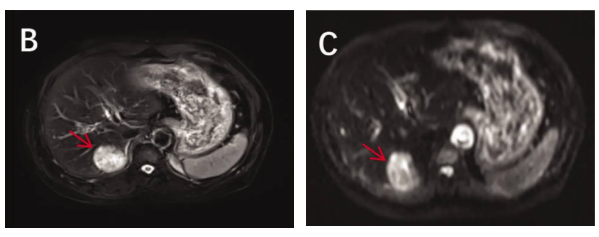

腹部MRI:肝VI-VII段交界区见一边界清晰的圆形病灶(大小46×36×32mm),动脉期呈高强化,门脉期及延迟期强化减退(“廓清征”),初步提示肝细胞癌

。

PET-CT:肝病灶、右肺门淋巴结及右肺上叶结节均表现为高代谢活性,符合转移性恶性肿瘤特征;胃肠道可见慢性炎症改变。

1 影像学诊断与生物标志物

增强CT和PET-CT是检测肝转移的主要手段,CT上肝转移灶通常表现为边缘不规则的低密度病变,PET–CT则显示明显的FDG摄取(最大标准化摄取值SUVmax > 9.0),反映了病灶的高代谢活性。与传统成像方式相比,⁶⁸Ga-PET-CT具有更高的肿瘤定位敏感性,能提升隐匿原发灶检出率及分期准确性,尤其在生长抑素

类似物治疗期间仍可维持诊断效能,建议对疑似神经内分泌肿瘤患者优先选用。此外,超声检查中出现的“驼峰征”(鹿角样钙化)也,有助于将LCNEC肝转移与其他肝脏恶性肿瘤相鉴别。